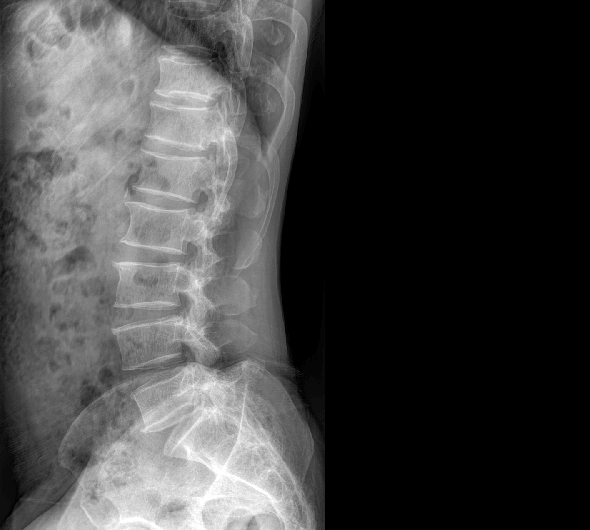

临床图像